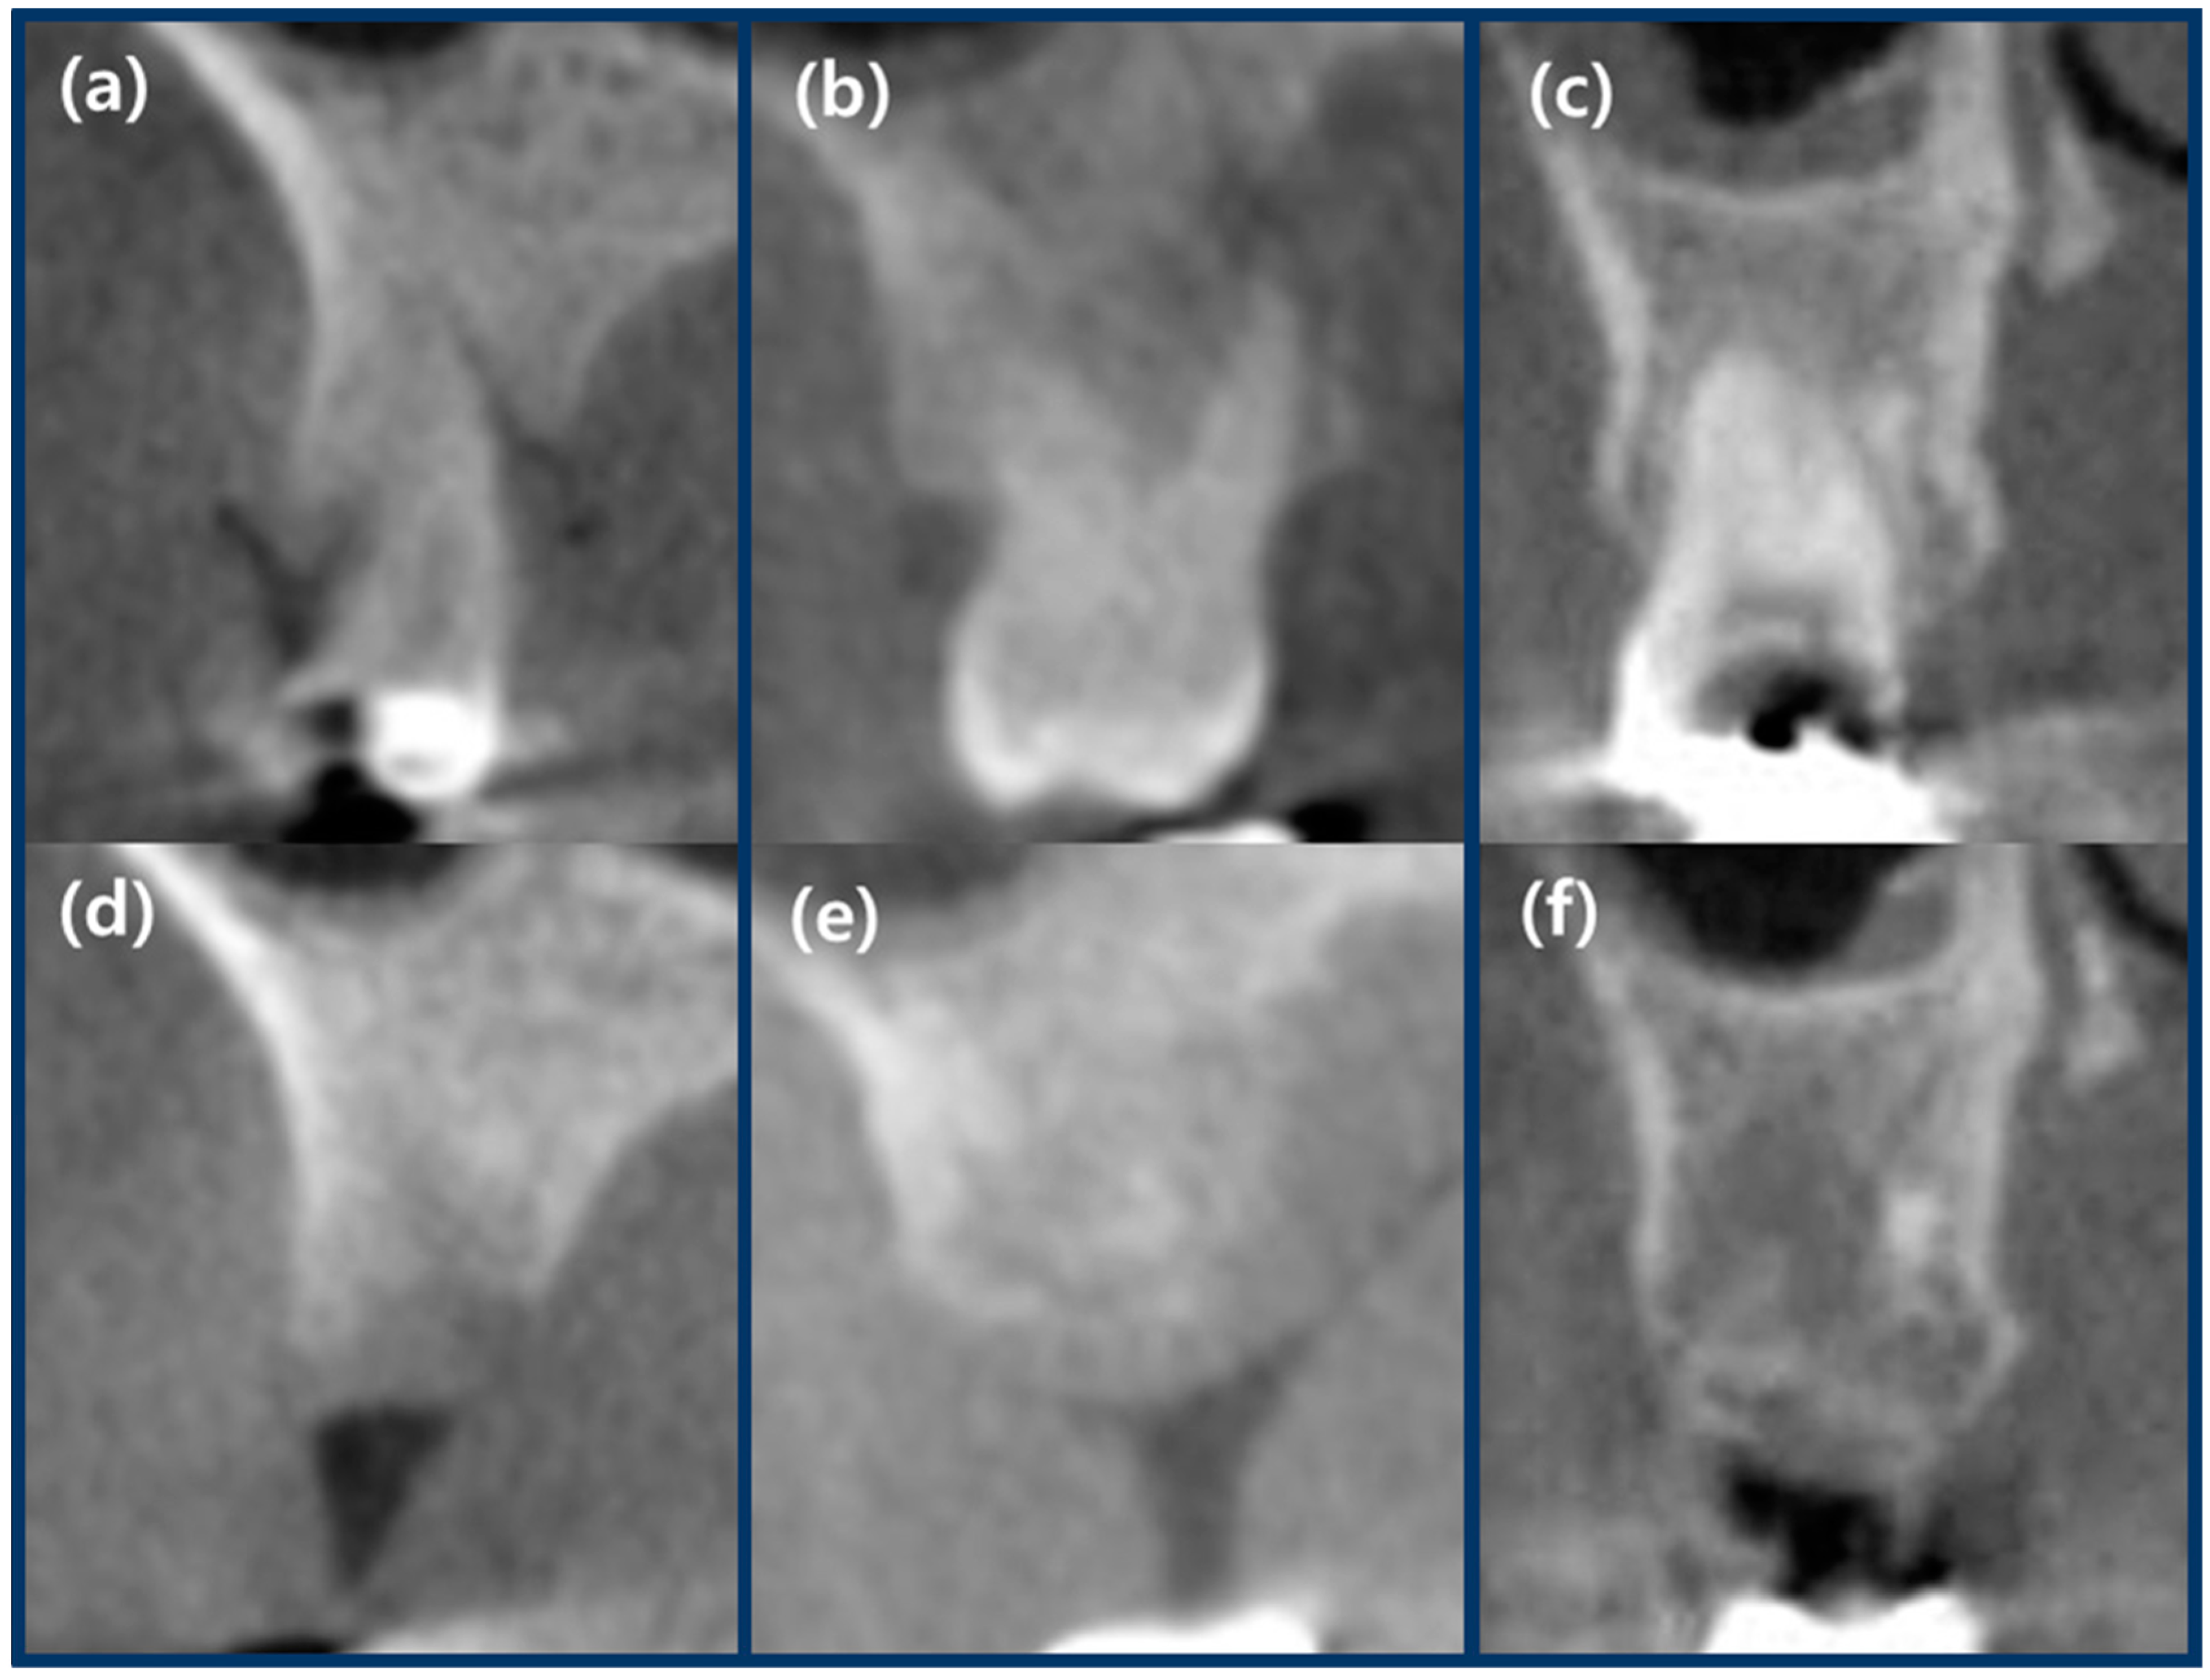

2.7. Radiographic Analysis Using CBCT

4. Discussion